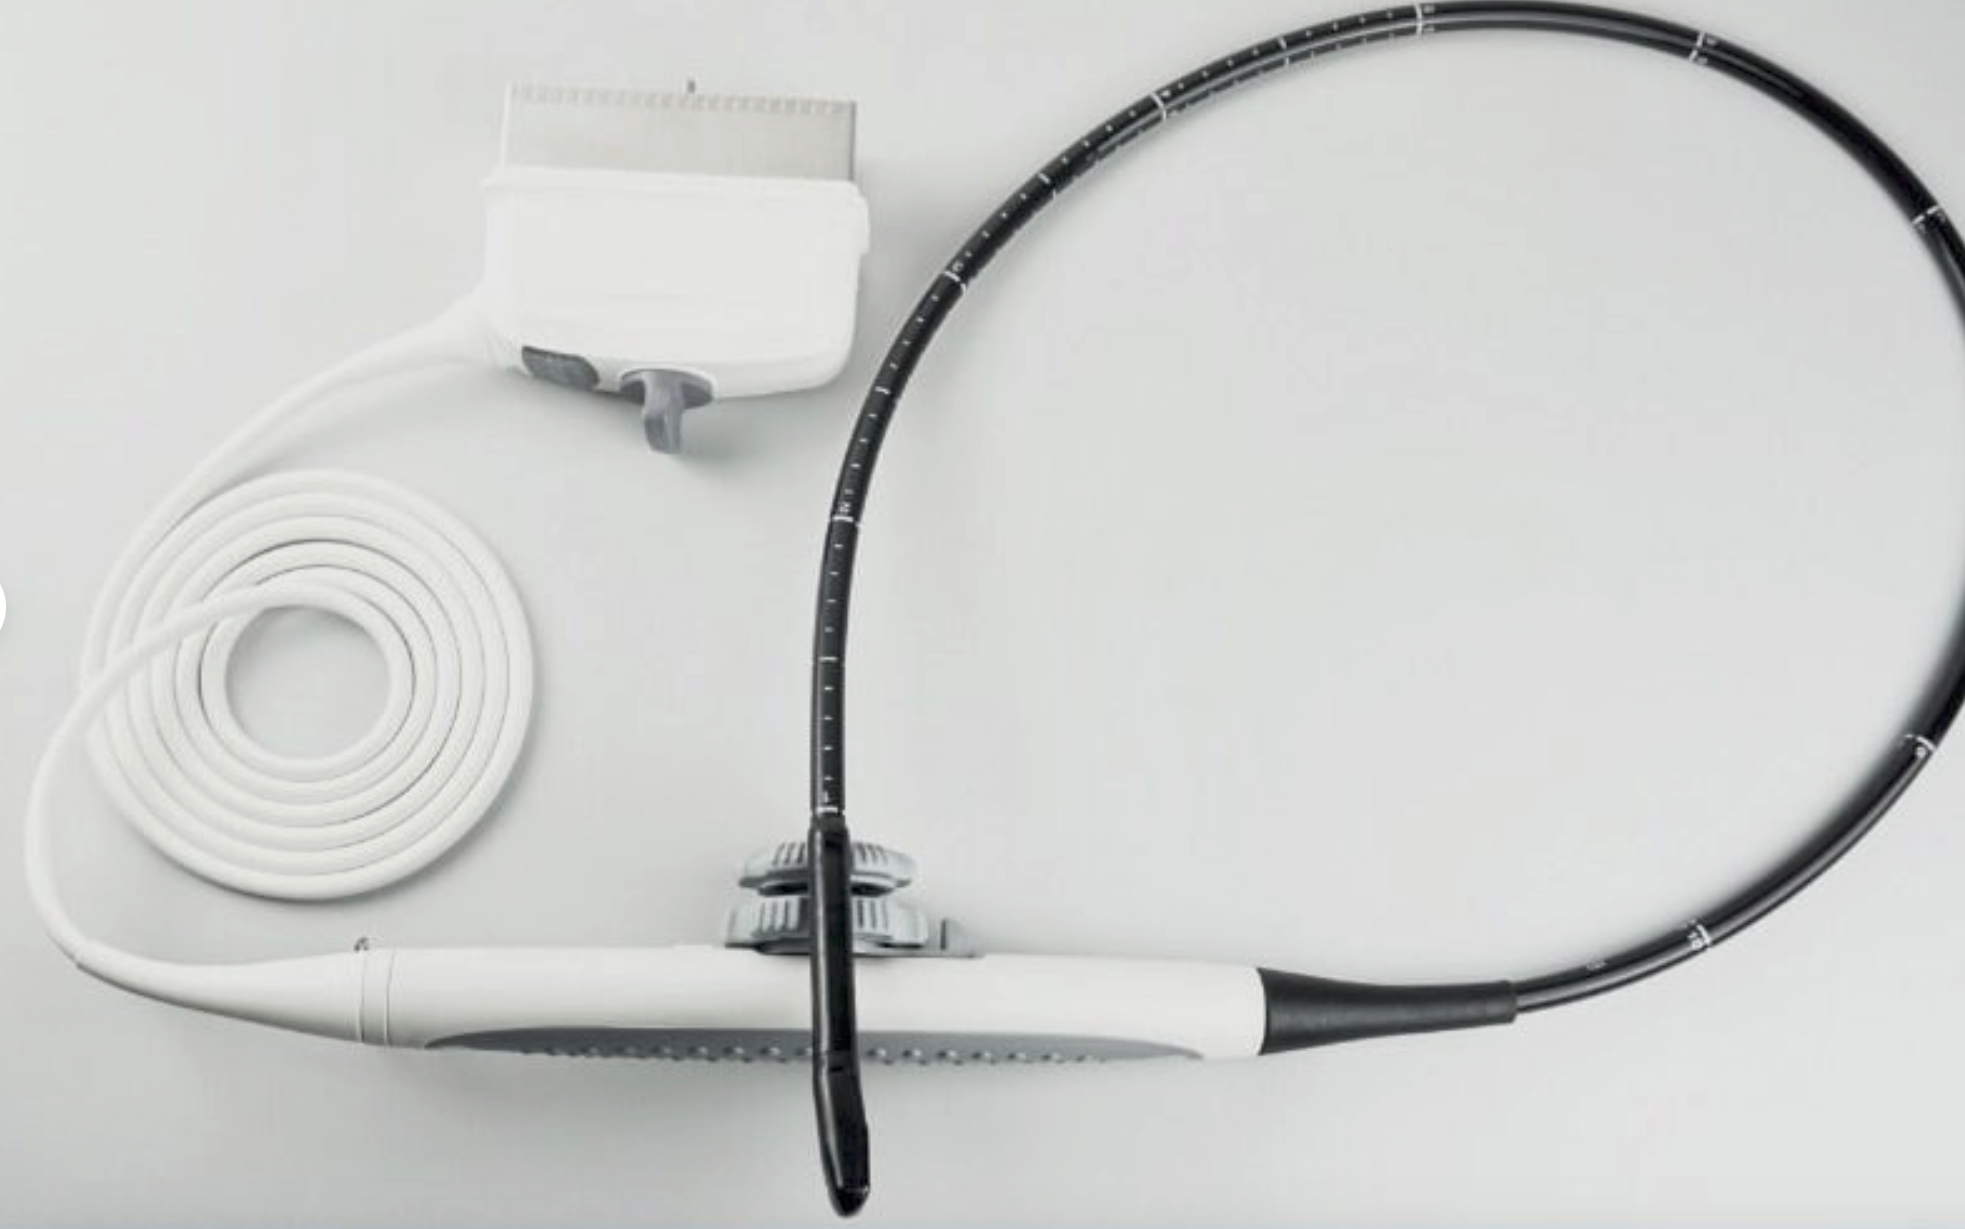

Probe: Convex + Linear + Micro convex heart 3 probes

The Laptop Ultrasound Scanner is an essential tool for healthcare professionals, as it combines Convex, Linear, and Micro Convex probes into one device. This versatility allows for a broad range of imaging applications, making it suitable for various medical settings. Whether you need to visualize abdominal organs or perform superficial assessments, this scanner meets and exceeds expectations. Because of its multiple probe options, medical practitioners can efficiently switch between different imaging modalities without the need for multiple devices.